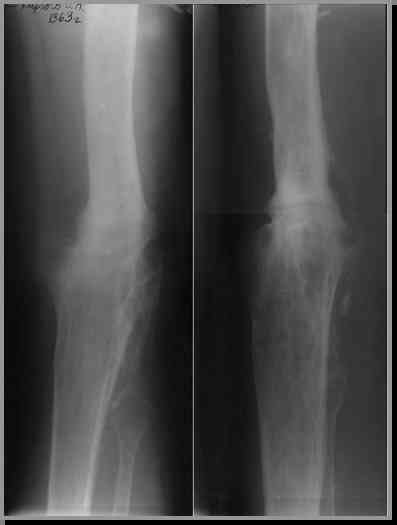

Этот стиль мне полностью приемлем и понятен. Наверно я бы поступил также. Но статистика упрямая вещь. Сколько у тебя или у другого врача опыта по замещению дефектов бедра? У меня за 25 лет работы 3, и еще около 15 случаев удлинения бедра. Случай у тебя очень сложный. Если Вы выбираете Илизаровскую методику то надо на в/з хорошую дугу, не менее 4-5 спиц с напайками.Стержни хороши когда кость не измучена и на 2-4 месяца. Здесь аппарат на 6-8 месяцев. Если есть желание я только за, и

Прикрепляю пример замещения дефекта бедра 20 см, после резекции по поводу опухоли, эндопротеза Сиваша, вялотекущего остеомиелита со свищами в течении 3 лет. Получилось хорошо и всего за 6 месяцев в аппарате. Колена не было. У Вас случай сложнее. Это было в 1998г. Я работал в ЦИТО и у меня было 4 больных, я занимался им с утра до ночи. Сейчас 60 больных и операций в нашем отделении 25-30 в неделю.Если могу чем помочь - нет проблем.